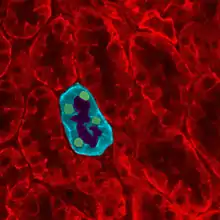

Glomerulus is red; Bowman's capsule is white.

Glomerulus is red; Bowman's capsule is white. Kidney tissue

Kidney tissue Glomerulus

Glomerulus This image shows the types of cells present in the glomerulus part of a kidney nephron. Podocytes, Endothelial cells, and Glomerular mesangial cell are present.

This image shows the types of cells present in the glomerulus part of a kidney nephron. Podocytes, Endothelial cells, and Glomerular mesangial cell are present.